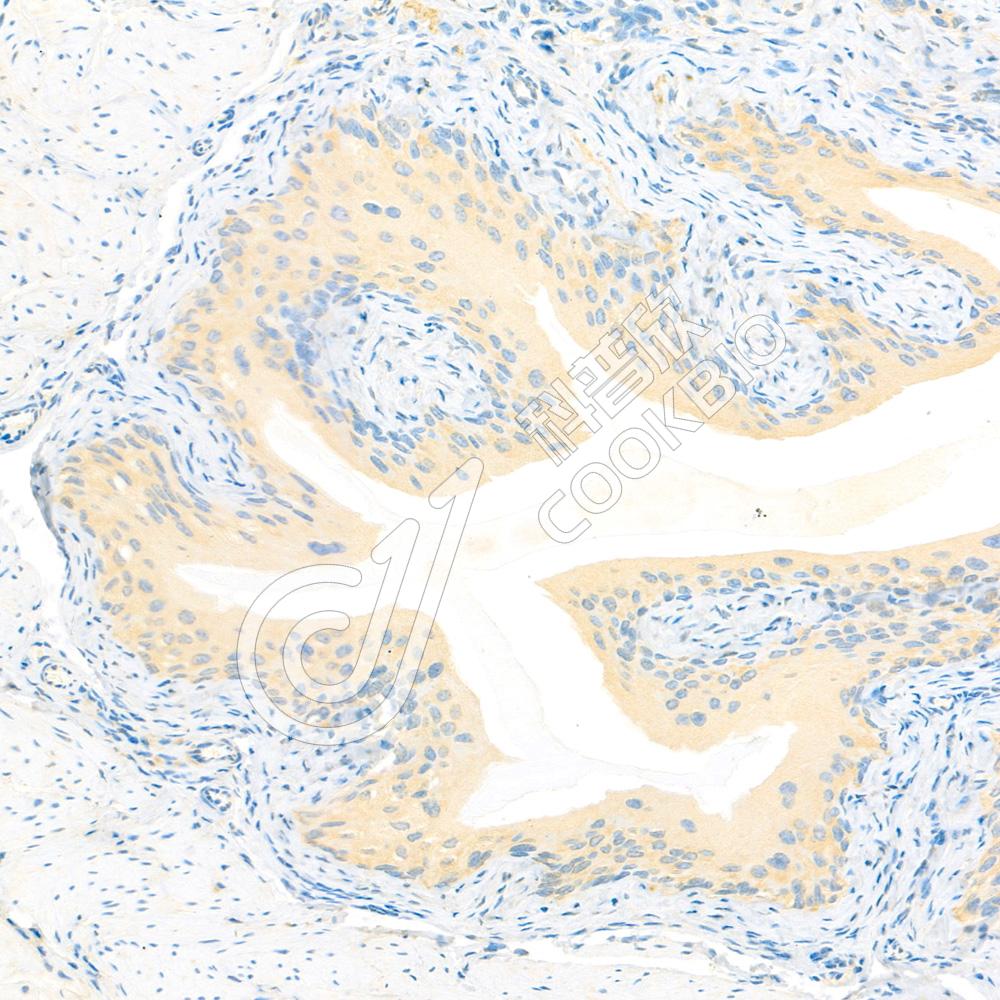

IF检测IL-10蛋白(货号 K133324)(绿色).

样品: 大鼠LPS诱导的脓毒症模型脾脏, 4%多聚甲醛 (货号KSG1101) 固定12-24小时.

抗原修复: Tris-EDTA抗原修复液(pH 9.0) (KSG1203), 98℃, 20分钟.

封闭: 3% BSA(货号KSGC305010)的PBS溶液, 室温孵育30分钟.

—抗: 1: 600稀释, 4℃ 孵育过夜.

二抗: Alexa Fluor 488标记山羊抗兔IgG (H+L) (货号KB75909), 1: 400稀释, 室温孵育1小时.